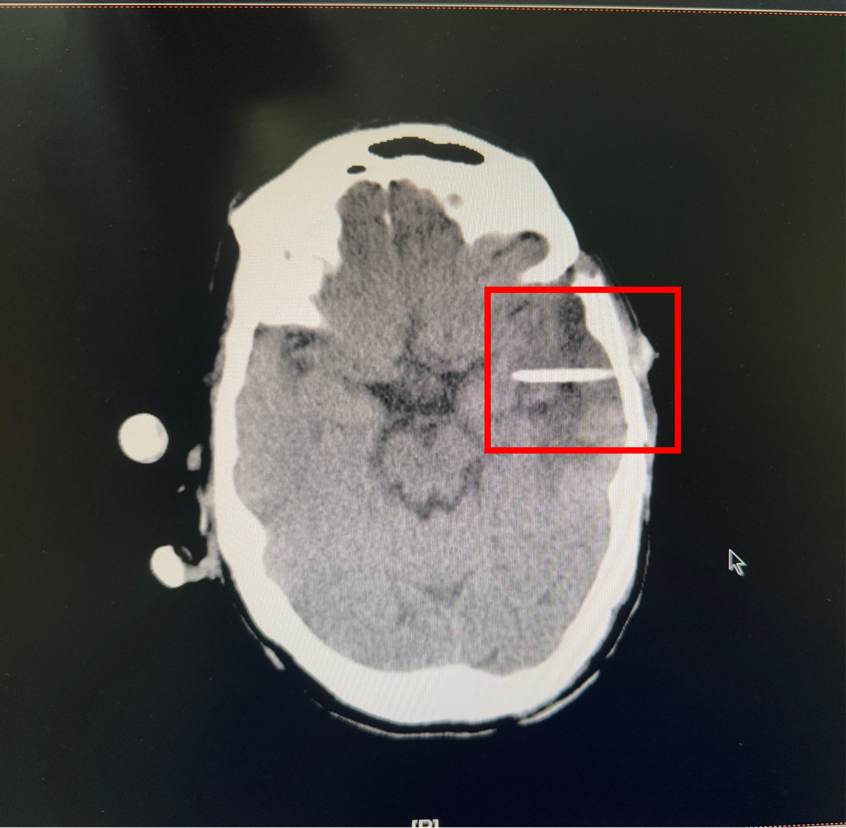

Ommaya 囊技术的应用,正是破解这一难题的「钥匙」。其核心是一个植入头皮下、连接脑室的微小储液器,其作用堪称一个精准的颅内「药物弹药库」。作为一个长期、可反复穿刺的药物输送通道,医生可以轻松地通过头皮穿刺这个「仓库」,将化疗药物、靶向药物或缓解症状的药物直接注入脑室或肿瘤周边,实现了药物的精准局部投送。这不仅大大提高了肿瘤局部的药物浓度,显著增强了对肿瘤细胞的杀伤效果,同时也避免了药物在全身循环带来的较大毒副作用,极大地改善了患者的治疗体验和生活质量。

此次接受手术的 3 位患者,均因病情需要建立了这一高效的局部治疗通道。手术过程顺利,患者术后恢复良好。Ommaya 囊的植入,为他们后续的规律性、个体化腔内化疗或靶向治疗奠定了坚实的基础,也为其战胜疾病带来了新的希望。